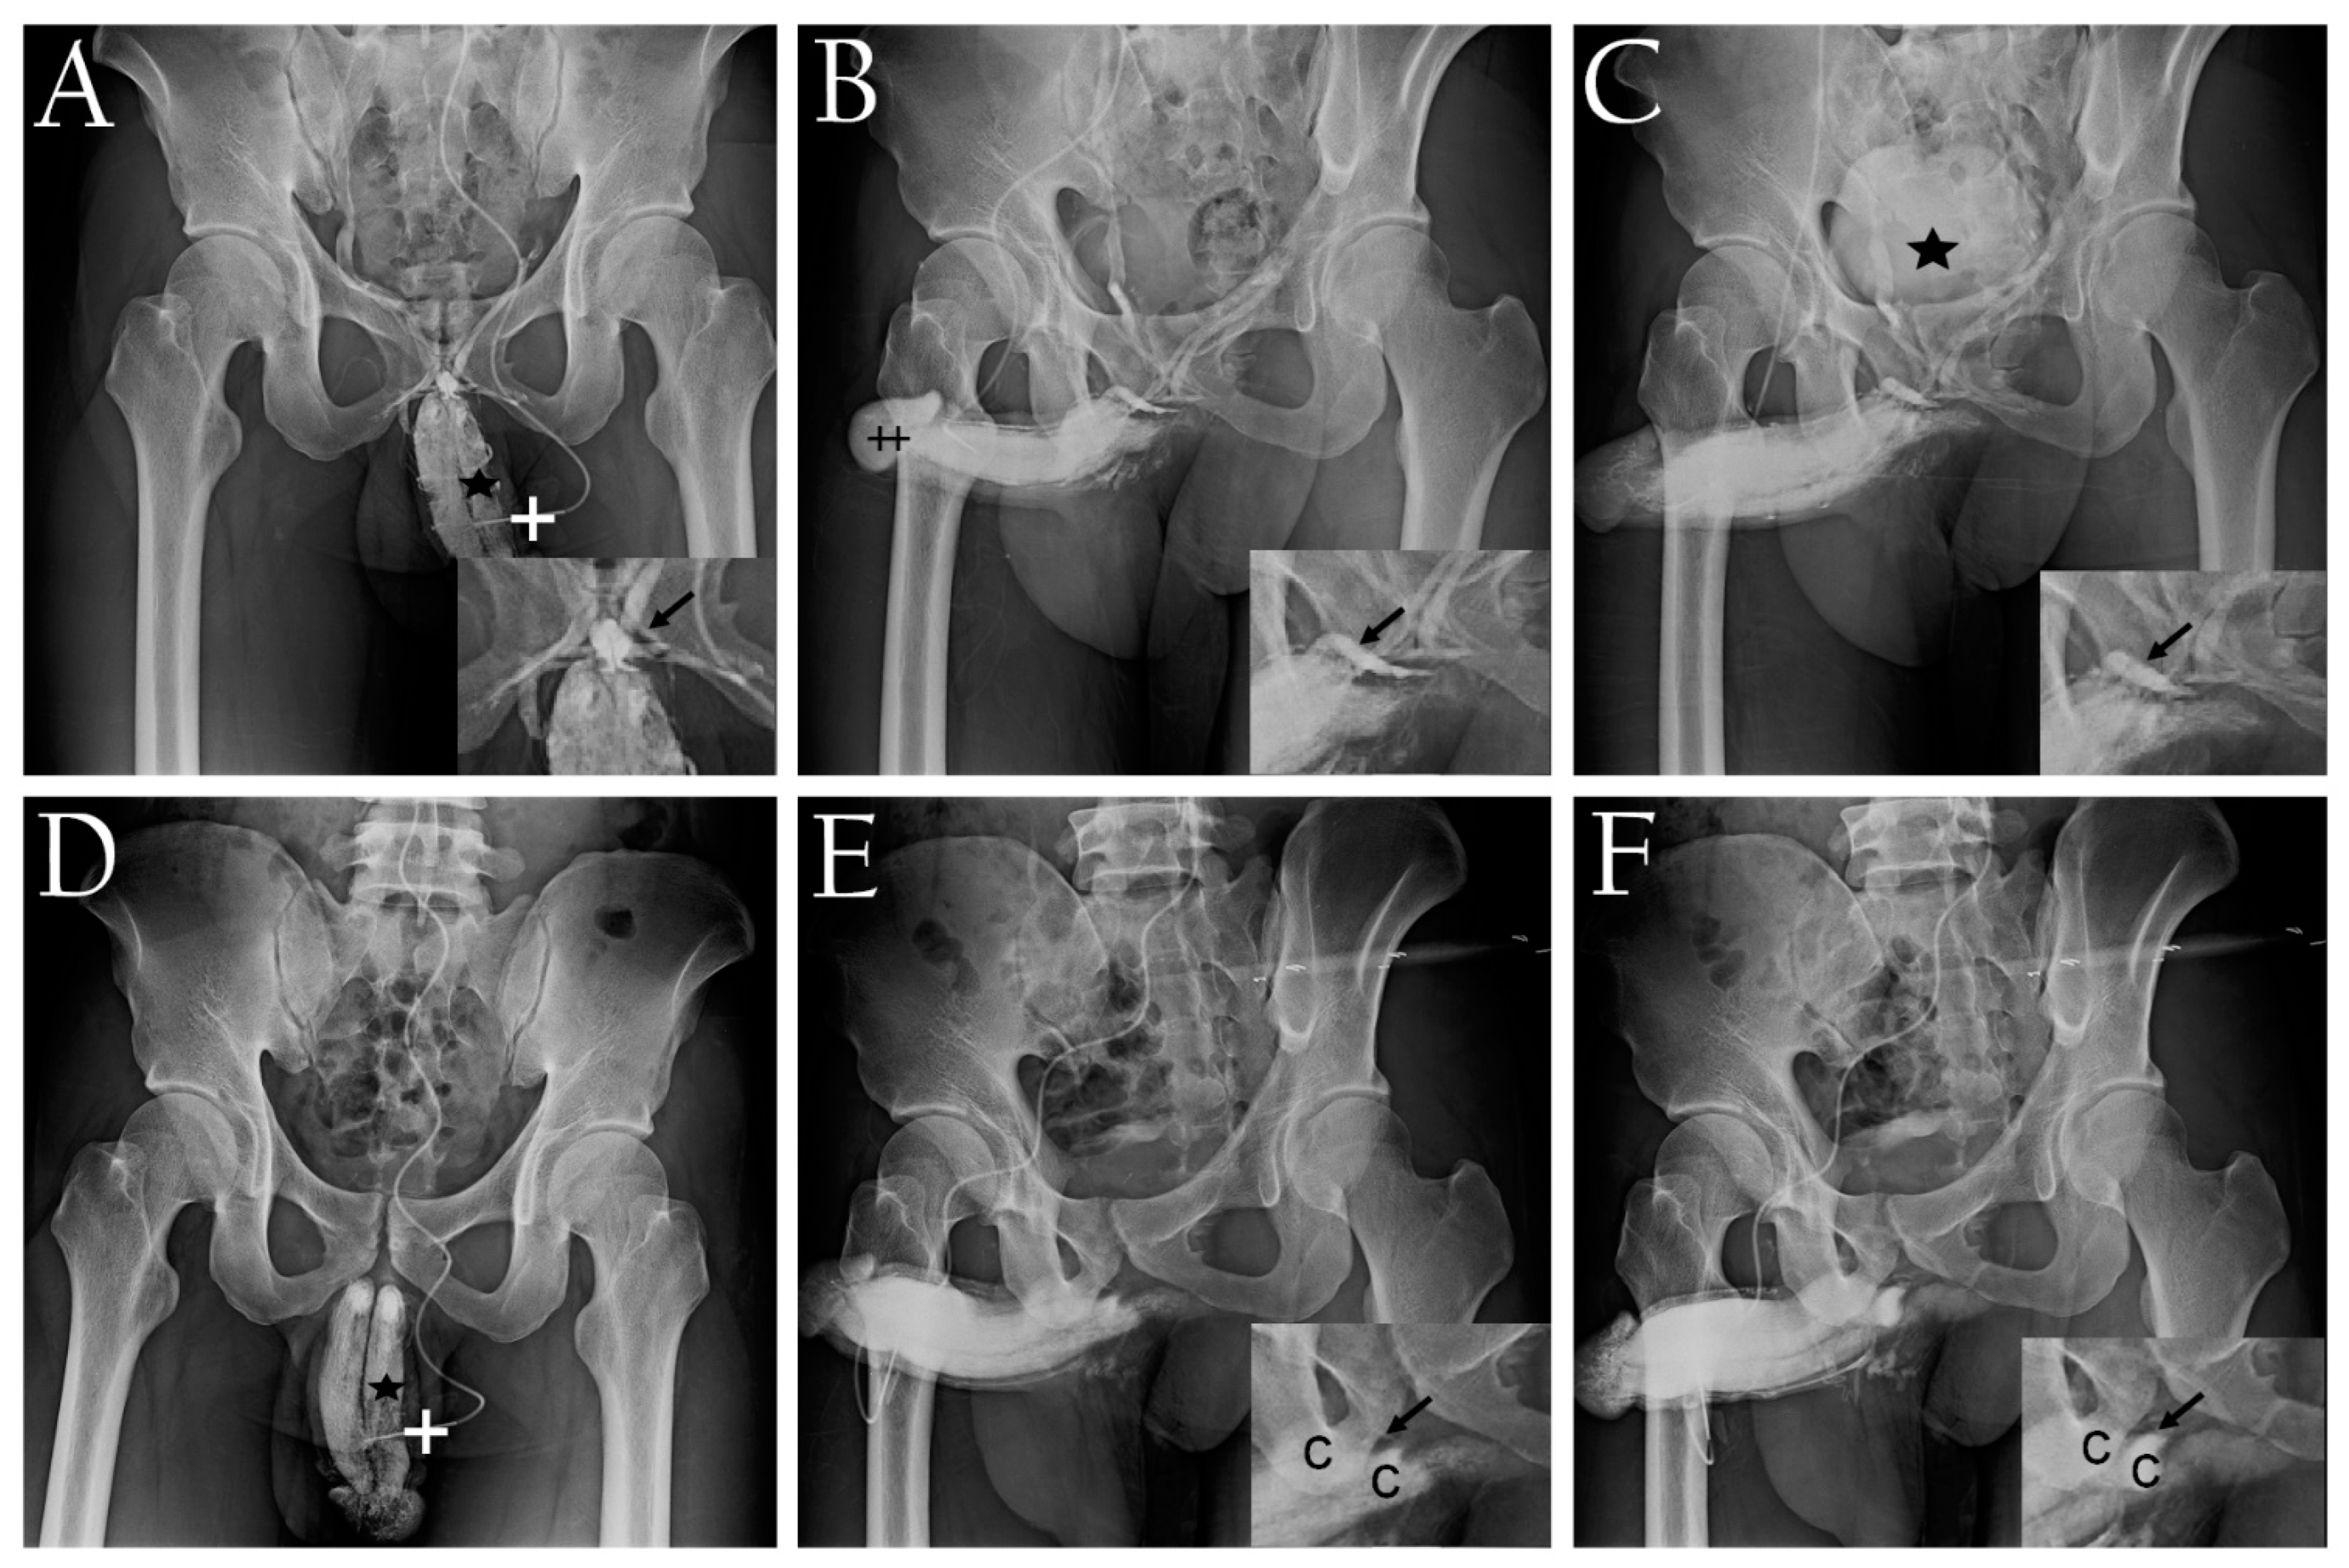

- Hsu, G.L.; Hill, J.W.; Chen, H.S.; Huang, S.J. Novel pilot films providing a dispensable information in pharmaco-cavernosography. Transl. Androl. Urol. 2014, 4, 398–405. [Google Scholar]